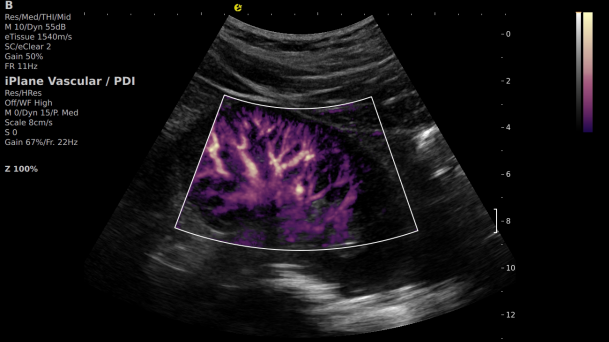

在肾移植领域,医生最怕的不是手术刀下的惊心动魄,而是那些手术后肉眼看不见的危机——急性排斥反应导致的血小板聚集形成的微血栓、毛细血管网损伤等...这些“隐形杀手”曾让无数移植肾在悄无声息中衰竭。而3377体育医疗(ESI)的iPlane Vascular平面波超微细血流显像技术,正是为破解这一难题而生。

这项革命性技术通过三大创新实现质的飞跃:

1) 基于OmniSound?平面波超快速平台,超声信号采集帧频提高了200倍(25000Hz)。

2) 可检测20-50μm级细小血管低速血流信号,能看清头发丝1/2粗细的微血管;

3) 通过血管指数(VI)定量评估局部血管密度,以定量化数据实时监测血流灌注情况,预判肾功能恢复情况;

超微视血流显像显示肾脏五级血管